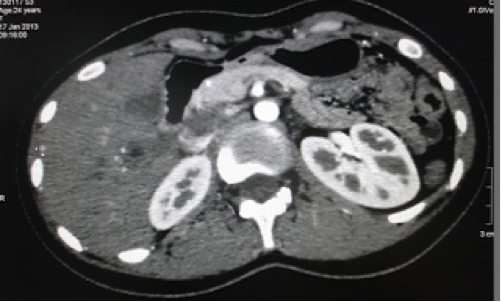

Bệnh nhân Lê Thị L. 27 tuổi, sống tại Rạch Giá được Bệnh viện đa khoa Kiên Giang chuyển đến Bệnh viện Từ Dũ lúc 23 giờ 30 phút ngày 27/08/2007; đã sinh 1 lần tại Bệnh viện Từ Dũ vào năm 2001. Trước nhập viện trên hai tháng, ngày 13/06, bệnh nhân đã được Bệnh viện đa khoa Kiên Giang mổ TNTC, cắt vòi tử cung phải; về nhà vẫn đau bụng âm ỉ, nhưng không đến khám lại. Từ ngày 20/08, bệnh nhân đau bụng âm ỉ vùng hạ sườn phải, siêu âm phát hiện thai trong ổ bụng, chuyển Bệnh viện Từ Dũ.

Tại Bệnh viện Từ Dũ, siêu âm và chụp CT tại Trung tâm Medic, phát hiện một thai sống khoảng 22 tuần trong ổ bụng vùng dưới hoành phải (dưới gan phải). Kích thước khối thai là 12x15x17cm. Bánh nhau dày 47mm, xâm lấn gan phải và có mạch máu nuôi xuất phát từ động mạch gan phải. Chẩn đoán: thai dưới gan, chỉ định mổ lấy khối thai và tiên lượng cuộc mổ khó nên mời phẫu thuật viên Bệnh viện Chợ Rẫy kết hợp cùng mổ.

Hình 6. Thai trong ổ bụng. Thai ngôi ngược, có hình ảnh giống như thai trong tử cung nhưng không rõ hình tử cung, khối thai nằm dưới gan nên thấy đầu các xương sườn (Nguồn: ảnh phim Medic) |